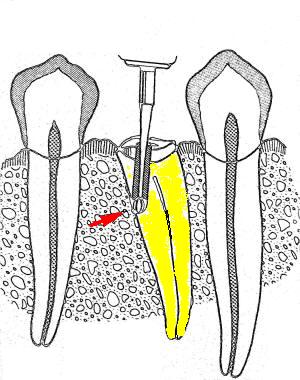

6-

Conductometría con RX:

consiste en determinar la longitud precisa entre el

CDC de cada

conducto y el borde incisal o la cara oclusal del diente en

tratamiento, considerando como longitud óptima 0,5 a 1mm. del ápice radiográfico

AR.

Pasos a

tener en cuenta

1.

Se

toma una radiografía inicial de diagnóstico

ortorradial, con el diente en el centro de la

placa, preferiblemente con técnica paralela. Se

mide la longitud de todo el diente desde el

borde incisal o cúspide oclusal hasta la porción

más apical del diente.

2.

resta 1 mm. a dicha longitud (distancia

existente entre ligamento periodontal y el CDC,

no observable en la radiografía). Conocer la

longitud promedio del diente es de gran ayuda

para determinar la longitud aproximada de

trabajo.

3.

Se desplaza el tope de silicona de una lima K

10 ( la elección del calibre de lima debe estar

relacionado con el espesor del conducto que

muestra la radiografía) y se aplica la longitud

radiográfica a la lima por medio de una regla.

4.

introduce la lima en el conducto correspondiente

hasta que el tope haga contacto con la

referencia anatómica elegida de la corona.

5.

toma una radiografía, una vez revelada se

verifica la ubicación del instrumento y se hacen

los ajustes necesarios, se considera que debe

estar ubicada a 0,5 – 1 mm del ápice

radiográfico.

6.

retira la lima del conducto y nuevamente se mide

la distancia entre el tope de goma y la punta

del instrumento, esta es la longitud de

trabajo definitiva. Se debe anotar en la

historia clínica las medidas de cada conducto y

el punto de referencia tomado para cada

conducto.

7.

Para conductos que se superponen es necesario

realizar la técnica de doble incidencia o

técnica de Clark, para desproyectar a los

conductos vestibulares del palatino o lingual.